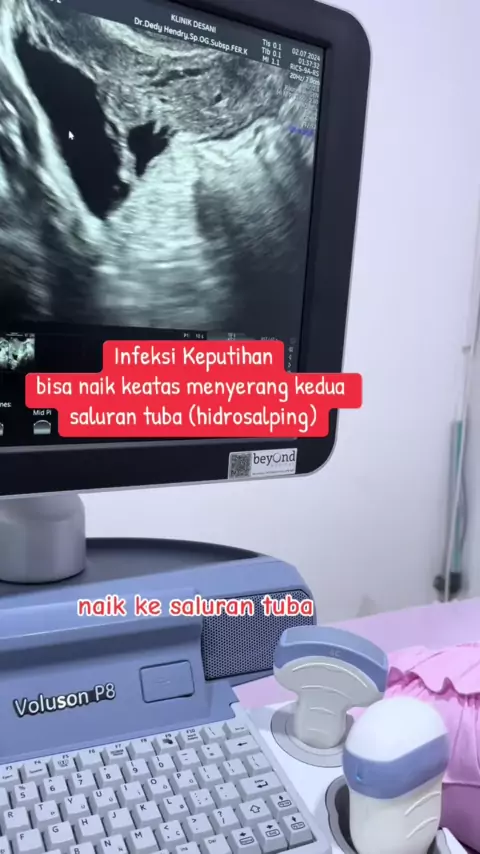

report 06/02-2026 Alhamdulillah setelah pasien ini melewati hari-hari yang berat dan panjang yaitu 2x mengalami operasi luar rahim (kedua tuba diangkat), menjalani program IVF sebelumnya dan gagal, baru datang keklinik kita @klinik_desani kemudian ditemukan adanya PCOS dan Adenomiosis, dilakukan IVF dan embrio yg didapatkan dilakukan PGTA dengan hasil keduanya perempuan (46 XX), transfer embrio beku dengan long protocol, alhamdulillah bisa hamil dan bagus jantungnya.. Alhamdulillah ya Allah @k...

kisah inspiratif dari provinisi Bengkulu Penantian 7 tahun.. gagal transfer embrio pertama kemudian datang menemui saya dan saya menemukan permasalahan utama pada pasien ini : endometrium yg selalu tipis ridak pernah mencapai 7 mm walapun sudah dilakukan berangai macam cara/protokol termasuk PRP endometrium @klinikdesani @Morula IVF Padang

9